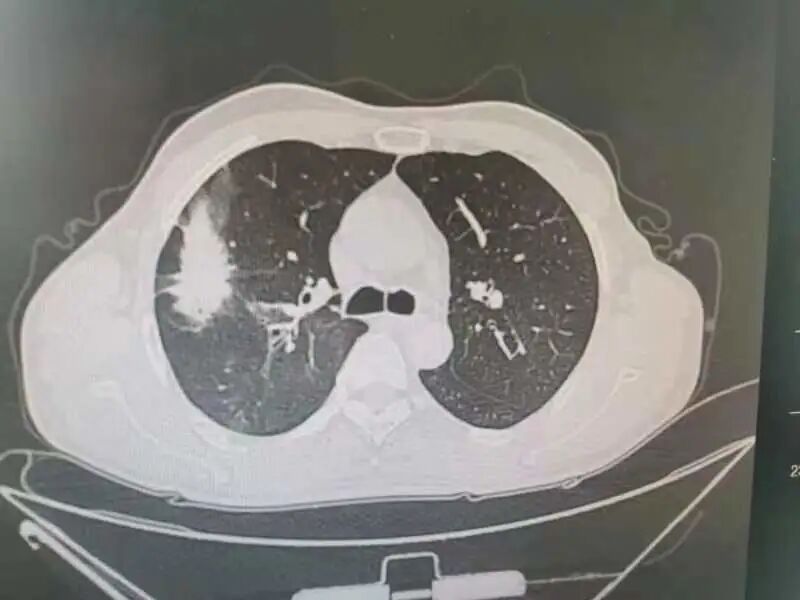

0岁的刘先生平时身体一直不错,登山、跳绳、骑行样样行。像他这样的年龄血压、血糖等都在正常值范围内,身体素质甚至比年轻的小伙子还好。因为没有这疼那痒,五年内从没体检过。 上个月不小心被车撞了一下,到辽宁省肿瘤医院拍了个肺部CT进行检查,这一查不要紧,除了受损的两根肋骨外,“眼尖”的医生居然在CT片子上发现了一个“恶魔”,在其右肺上叶有一个接近5cm的肺结节。 影像资料 辽宁省肿瘤医院胸外科团队接诊后,耐心地询问刘先生,可刘先生既没有吸烟史也没有癌症家庭史,每天在公园暴走上万步的刘先生,会跟“肺癌”这两个字联系在一起吗? 影像资料 为了不给刘先生及其家属带来恐慌,又不能耽误病情,胸外科团队请来了专家为其进行多学科会诊(MDT),“我们不敢冒然行事,也不敢错过手术最佳时机,因为从这个肺结节的形态上来看,如果是肺癌的话,行手术根治术+淋巴清扫,预后效果应该还是不错的”。 手术中 经多学科会诊,专家们建议为刘先生行CT引导下穿刺,以进一步明确病理。病理结果出来后,跟专家们的预想差不多,病理提示“肺腺癌”,胸外科为刘先生做了单孔胸腔镜下的肺癌根治术+淋巴清扫术。术后刘先生恢复很快,5天就出院了。因为是早期肺癌,发现得早,及时手术切,刘先生并不需要化疗、放疗,刘先生悬着的心终于放下了,说道“要不是这场车祸,不然还不知道什么时候会发现,也有可能发现时就是晚期了呢” 早期肺癌治愈率高,定期体检是关键。祸兮福之所倚,福兮祸之所伏。短短一个月内,刘先生经历了“车祸——肺结节——肺癌——手术根治”的跌宕人生。像刘先生这样因为外伤检查住院而意外发现早期肺癌的患者,医院也收治了不少。因为早期肺癌相当隐匿,几乎没有什么症状。如果缺乏定期体检,不做胸部CT,早期肺癌是难以发现的。而等患者发现时就已经到了中晚期了,不仅治疗复杂费钱,效果还不好。 辽宁省肿瘤医院胸外科专家介绍,早期肺癌治愈率较高,其中原位癌及微浸润腺癌治愈率可达90%--100%,且不需要放疗、化疗,治疗费用低,生存质量也高。而中晚期肺癌的五年生存率只有20%--50%。所以,定期体检非常重要。但值得注意的是,大部分肺结节是良性的,只有30%--40%的肺结节可能是早期肺癌。即便是早期肺癌,通过微创手术切除治疗效果也较好。